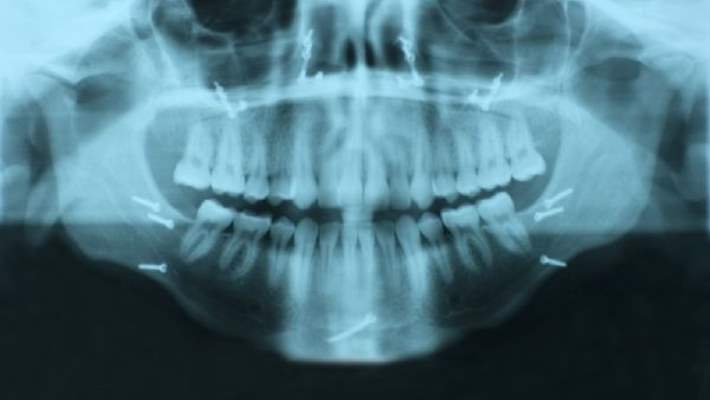

- çene kırığı

Kırık kemiğin ciltten ya da ağız içinden görülebildiği ve ‘açık kırık olarak adlandırılan durumlar, hastaneye yatmayı ve damardan antibiyotik verilmesini gerektirir. çoğu zaman, eğer kapalı çene kırığınız varsa, tedavi için bir ağız cerrahına yönlendirilirsiniz.